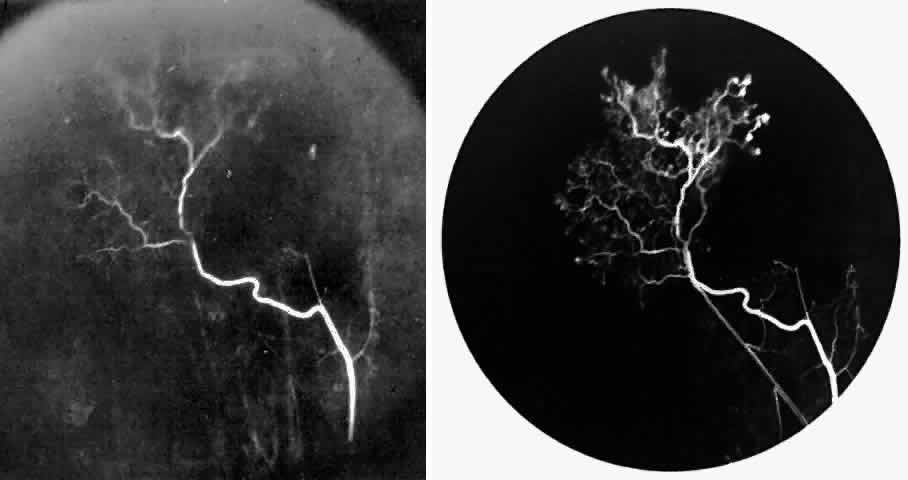

STAGE II: PERIPHERAL ARTERIOLAR-VENULAR ANASTOMOSES. Following occlusion of the terminal arterioles, anastomotic channels form to channel the blood from the occluded arteriole to the nearest venules. These anastomoses form at the interface between the perfused and nonperfused retina. Most likely, they are dilated preexisting capillaries rather than new vessels, since they do not leak on fluorescein angiography. The redirection of blood flow is probably due to hydrostatic forces (Figs. 22 and 23).

|

STAGE III: PRERETINAL NEOVASCULARIZATION (PROLIFERATIVE SICKLE RETINOPATHY). “Sea fan”-shaped neovascularization typically develops on the venular side of an arteriolar-venular anastomosis, mimicking the normal development of retinal capillaries (Fig. 24).125 A lowered oxygen tension and angiogenic factors released on the venular side may be the stimulus for neovascular growth.125,126 In most instances, the direction of growth is toward the ora serrata, from the perfused retina toward the nonperfused retina. Presumably, this represents an abortive attempt to revascularize the nonperfused retina, initiated by vasoproliferative factors.

The characteristic neovascular lesions of PSR are called sea fans because they resemble the marine invertebrate Gorgonia flabellum.70 They tend to occur more commonly in the temporal periphery, but they have been reported to occur in the temporal macula in the presence of extensive nonperfusion.130,133 Initially they grow on the surface of the retina, but they often become elevated into the vitreous and adhere to a partially detached posterior hyaloid.114 It may be difficult to visualize small sea fans ophthalmoscopically; however, fluorescein angiography clearly demonstrates leakage of dye into the vitreous (Fig. 25). The feeding arteriole is usually more tortuous than the draining venule (Fig. 26). Early on, the neovascular lesion is fed by a single arteriole and drained by a single venule, but with time, additional arterioles and venules become arborized within the lesion (Fig. 27).129 Growth of the sea fan often occurs circumferentially, rather than radiallyÜmh- 1Ý, toward the ora serrata. Progressive circumferential growth may lead to neovascular lesions extending around the entire periphery. As it matures, a white fibroglial mantle often covers the neovascular tissue (Color Plate 2B).